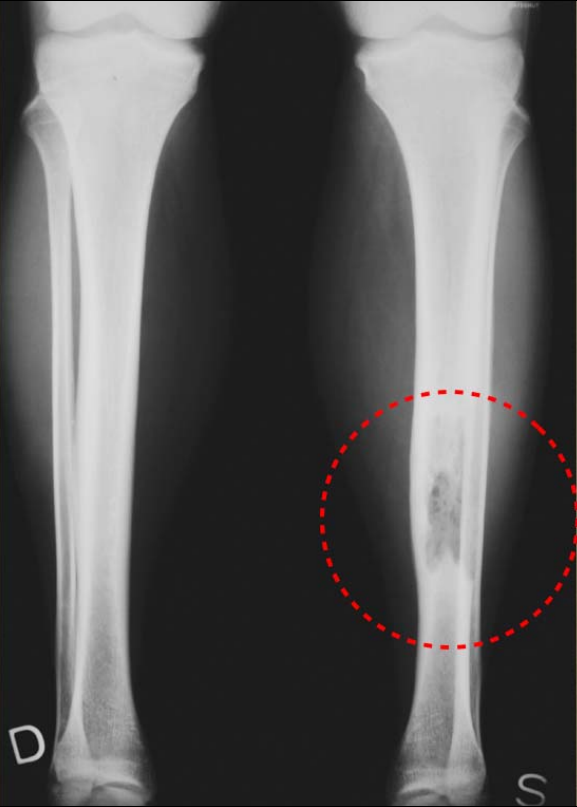

Figure2